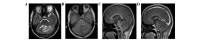

Lhermitte-Duclos disease (LDD) is a rare, non-cancerous entity characterized by enlarged, abnormally developed cerebellar folia containing dysplastic cells. Symptomatic LDD is commonly observed in adults (adult-onset LDD, aLDD) as an isolated condition or associated with Cowden's disease (CD). The present study aimed to investigate the magnetic resonance imaging (MRI) characteristics and the underlying pathological findings in 7 cases of aLDD, with emphasis on the association with CD and the need for active cancer surveillance once the diagnosis of LDD is confirmed. The MRI findings along with the clinical and histopathological data collected from 7 patients with aLDD were retrospectively reviewed. The diagnosis of CD was based on a range of clinical characteristics, according to the International Cowden Consortium Criteria. A thorough review of the published data was conducted and our results indicated that all 7 cases shared similar MRI characteristics, whether the aLDD was sporadic (2 cases) or associated with CD (5 cases), including a highly typical non-enhancing striated MRI appearance of thickened folia, consisting of alternating bands on T1- and T2-weighted images. On gross examination, the involved cerebellar folia were distorted and enlarged, whereas the histopathological examination revealed that the molecular layer was widened and occupied by abnormal ganglion cells. Moreover, a reduction in the number or absence of the Purkinje cells and hypertrophy of the granular cell layer were observed. Our findings were consistent with the diagnosis of LDD. Variable levels of vacuolization of the white matter and the molecular layer were observed in all the cases. Notably, CD34 immunohistochemical analysis revealed the presence of angiogenesis within the lesions. aLDD associated with CD exhibited no pathological or immunohistochemical characteristics that were distinct from those of isolated aLDD. Of the 7 cases of aLDD, 5 presented with symptoms suggestive of CD, which is a syndrome associated with a high risk of multiple benign and malignant neoplasms. In conclusion, aLDD exhibits characteristic MRI and histopathological findings and displays a strong association with CD. Therefore, we recommend that the MRI diagnosis of aLDD triggers active cancer surveillance and preventive care.